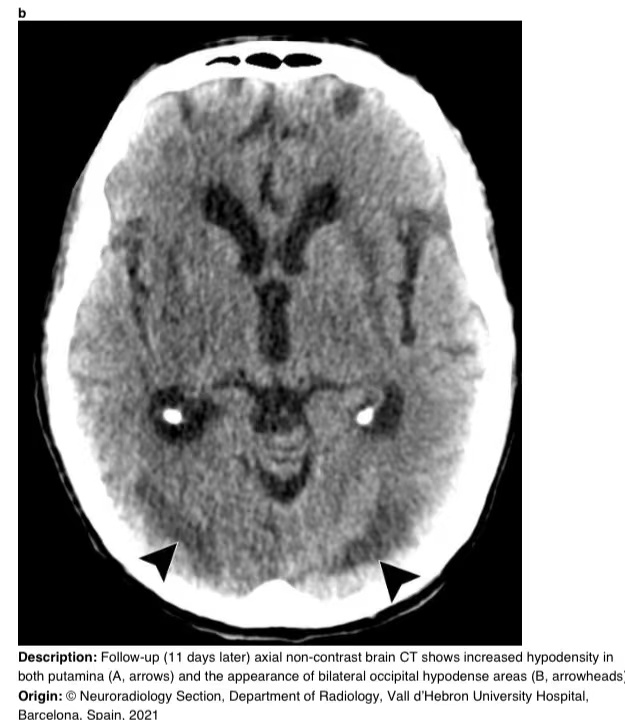

在16天的随访中,脑部MRI显示壳核和枕下皮质下白质上对称的T2/FLAIR高信号。T2图像显示病变内有微出血(图3)。

图3 a-h 脑部核磁共振成像。轴向T2加权(A-B)、轴向T2 FLAIR加权(C-D)、轴向弥散加权(E-F)和轴向T2图像(G-H)。T2加权和T2 FLAIR加权图像显示双侧和对称的壳核高信号(A和C,箭头)和枕下皮质下白质高信号(B和D,箭头),无弥散限制(E-F)。在T2图像上,病变内有一些微出血病灶(G-H,箭头)。